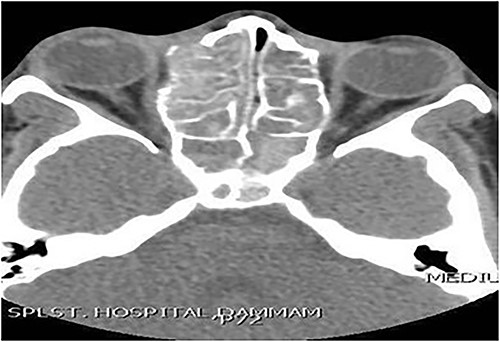

Case 3 (bilateral)

A 14-year-old male presented with a history of bilateral nasal obstruction for 3 years associated with snoring and postnasal discharge. Endoscopic examination showed bilateral nasal polyposis. CT scan of the paranasal sinuses (Fig. 3) & FESS, via which the sinuses were found full of polyps, mucin and fungal debris, confirmed the diagnosis of bilateral AFS. The patient continued on postoperative medical treatment and remained symptoms-free for 2 years follow-up.

Axial CT paranasal sinuses shows heterogeneous opacities filling the ethmoid and sphenoid sinuses bilaterally with hyperdense contents. The ethmoid sinus shows expansion with partial dehiscence of the right lamina papyracea.